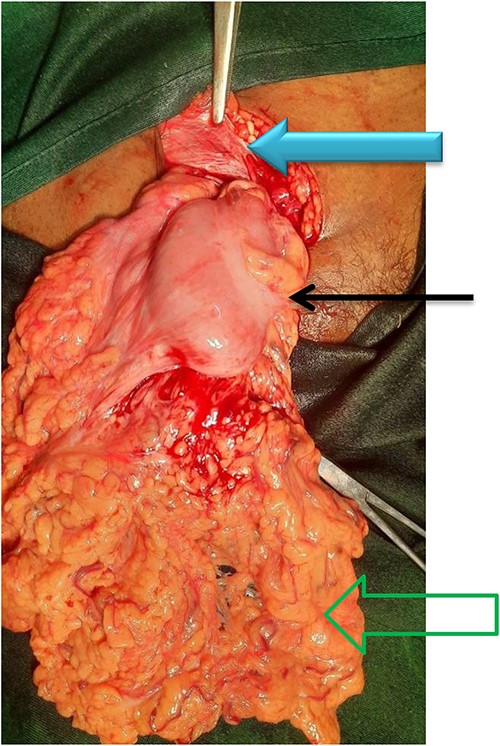

Under spinal anesthesia, trans-inguinal approach was made, and the hernia neck was visualized but difficult to reduce from that point. For this reason, infra-inguinal extension was made subcutaneously and the sac was approached, and the adherent sac was dissected and opened. The finding showed an incarcerated omentum and part of the transverse colon in the hernia sac with few adhesions otherwise viable (Fig. 2). Part of the incarcerated omentum was resected out as it was difficult to reduce in-mass. Then, the transverse colon reduced back safely to the abdominal cavity. High ligation of the sac and fixing of the pectinet ligament to the inguinal ligament were performed with an interrupted non-absorbable suture. The posterior wall of the inguinal floor was reconstructed and the inguinal ligament was strengthened to conjoin the tendon for prophylaxis purpose. The operation was performed by a consultant surgeon in a government hospital.

The content of the sac along with its contents (green open arrow shows viable omentum, black solid arrow shows transverse colon, and solid blue arrow shows an inguinal ligament).